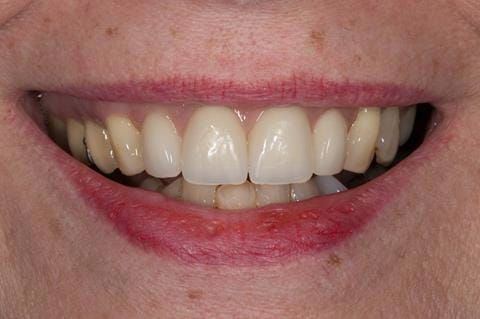

- High smile line showing gum above gingival zeniths of upper front teeth when smiling. Aesthetic failure of the upper four incisors with inflammation of the gingivae and mis-match of the gingival zenith levels.

Following consultation and second discussion appointment the patient chose to have option 3 namely, a maxillary cobalt chromium based partial denture/protective occlusal splint. The clinical situation and treatment process is shown in detail below with photographs. The patient was successfully rehabilitated with this and her quality of life considerably improved. The clinical work was provided by Finlay and the technical work by Rowan.